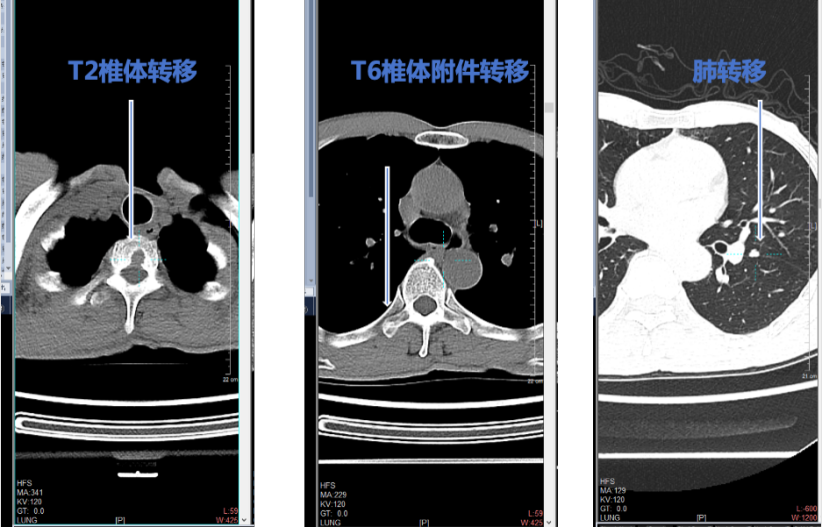

术后复查:2024-01-12复查,发现肺部、骨多发转移,甲状腺球蛋白明显增高。

图6 复查发现肺部、骨多发转移

辅助检查及疗效评价:分别于2024-04-28、2024-09-27、2024-11-07持续影像评估,肺转移灶迅速退缩至接近CR(图7),骨转移灶于用药后第4周(2024-04-28)复查有进展,用药半年后明显修复(图8、图9)。接受伊鲁阿克治疗后,甲状腺球蛋白TG迅速降低(图10)。

图8 T2椎体病灶改变

图9 T6椎体病灶改变

在本病例中,伊鲁阿克治疗初期,骨转移灶有进展,但治疗6个月后病灶明显修复,与此同时,在治疗初期,肺转移灶就展现出了对于治疗的积极反应。这种动态变化引发了我们对伊鲁阿克作用机制及其对于不同部位转移灶疗效差异的深入思考。

值得注意的是,本病例中,伊鲁阿克治疗后,骨转移灶在治疗初期进展,但随着治疗的持续进行,最终也展现出了修复的迹象。这表明伊鲁阿克对不同部位转移灶的作用机制在本质上是相同的,即通过抑制ALK信号通路来抑制肿瘤细胞的生长和增殖。只是由于肿瘤异质性的存在,不同转移灶对伊鲁阿克的反应时间和程度存在差异。

既往的临床经验认为,在甲状腺癌远处转移的靶向治疗中,多靶点酪氨酸激酶抑制剂对骨转移灶的治疗效果欠佳,但在本病例中,伊鲁阿克在治疗多部位转移灶时展现出了良好的疗效。这进一步证明了伊鲁阿克作为一种高选择性ALK抑制剂的独特优势,其在控制肿瘤进展、延长患者生存期方面具有重要的临床价值。